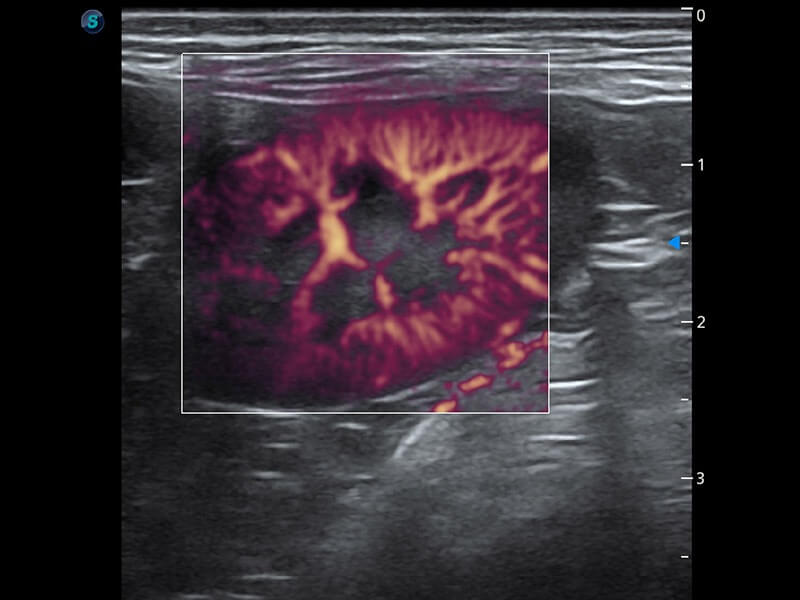

ProPet 60 作为一款高端台式动物超声设备,为动物医生的日常诊断提供了一系列贴合动物临床需求、解决临床实际问题的高级成像功能。凭借全系列高清探头,满足医生对腹部、心脏、生殖、浅表、肌骨等成像的所有需求,切实帮助您提升检查效率,提高诊断信心。

兽用彩色多普勒超声诊断系统